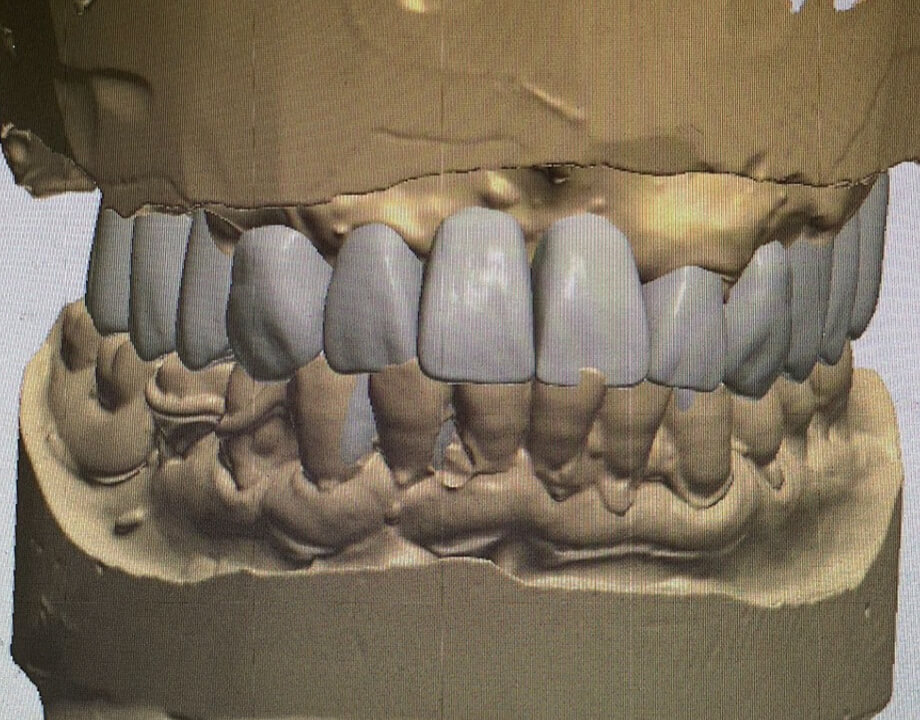

Case 06咬合再構成

デジタルワックスアップ

→シュミレーション(SMOP)

→プロビジョナル

→最終補綴物(モノリシックジルコニアAGC)